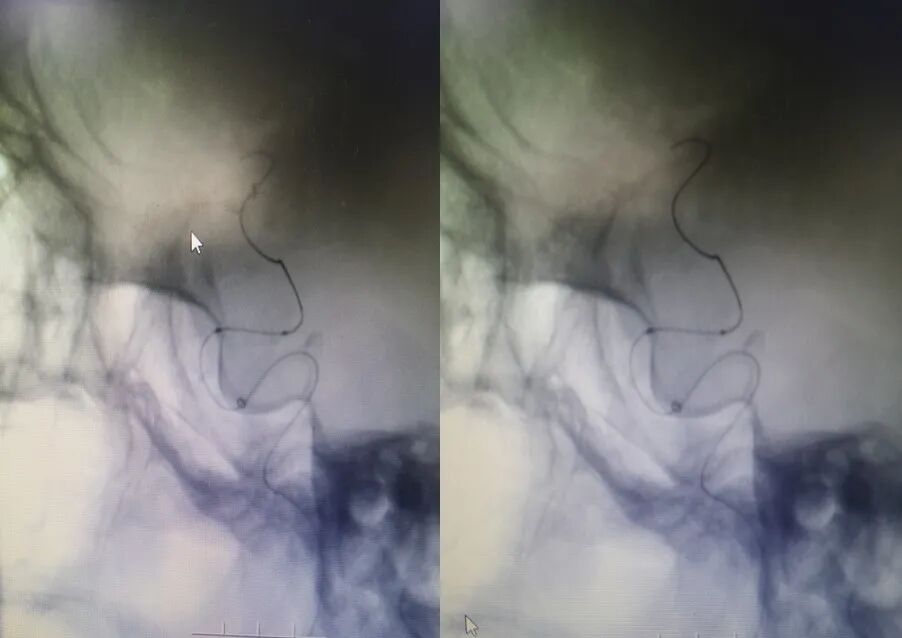

入院影像检查

导丝怎么扩【载药时代 球扩天下】NOVA DES®颅内药物洗脱支架在症状性颅内动脉狭窄中的应用—烟台鲁东医院使用体会二例!_https://www.jmylbn.com_新闻资讯_第19张

重要影像结论:右侧颈内动脉C6段重度狭榨。

重要影像结论:右侧颈内动脉C6重度狭窄(90%)。

病变部位:右侧颈内动脉C6段

远端正常血管直径(mm):3.1

狭窄处最小直径(mm):0.5

病变长度(mm):10

狭窄度(%):90%以上

导丝怎么扩【载药时代 球扩天下】NOVA DES®颅内药物洗脱支架在症状性颅内动脉狭窄中的应用—烟台鲁东医院使用体会二例!_https://www.jmylbn.com_新闻资讯_第20张

导丝怎么扩【载药时代 球扩天下】NOVA DES®颅内药物洗脱支架在症状性颅内动脉狭窄中的应用—烟台鲁东医院使用体会二例!_https://www.jmylbn.com_新闻资讯_第21张

术后影像及检查

影像结论:血管成形良好,支架贴壁良好,远端显影良好。